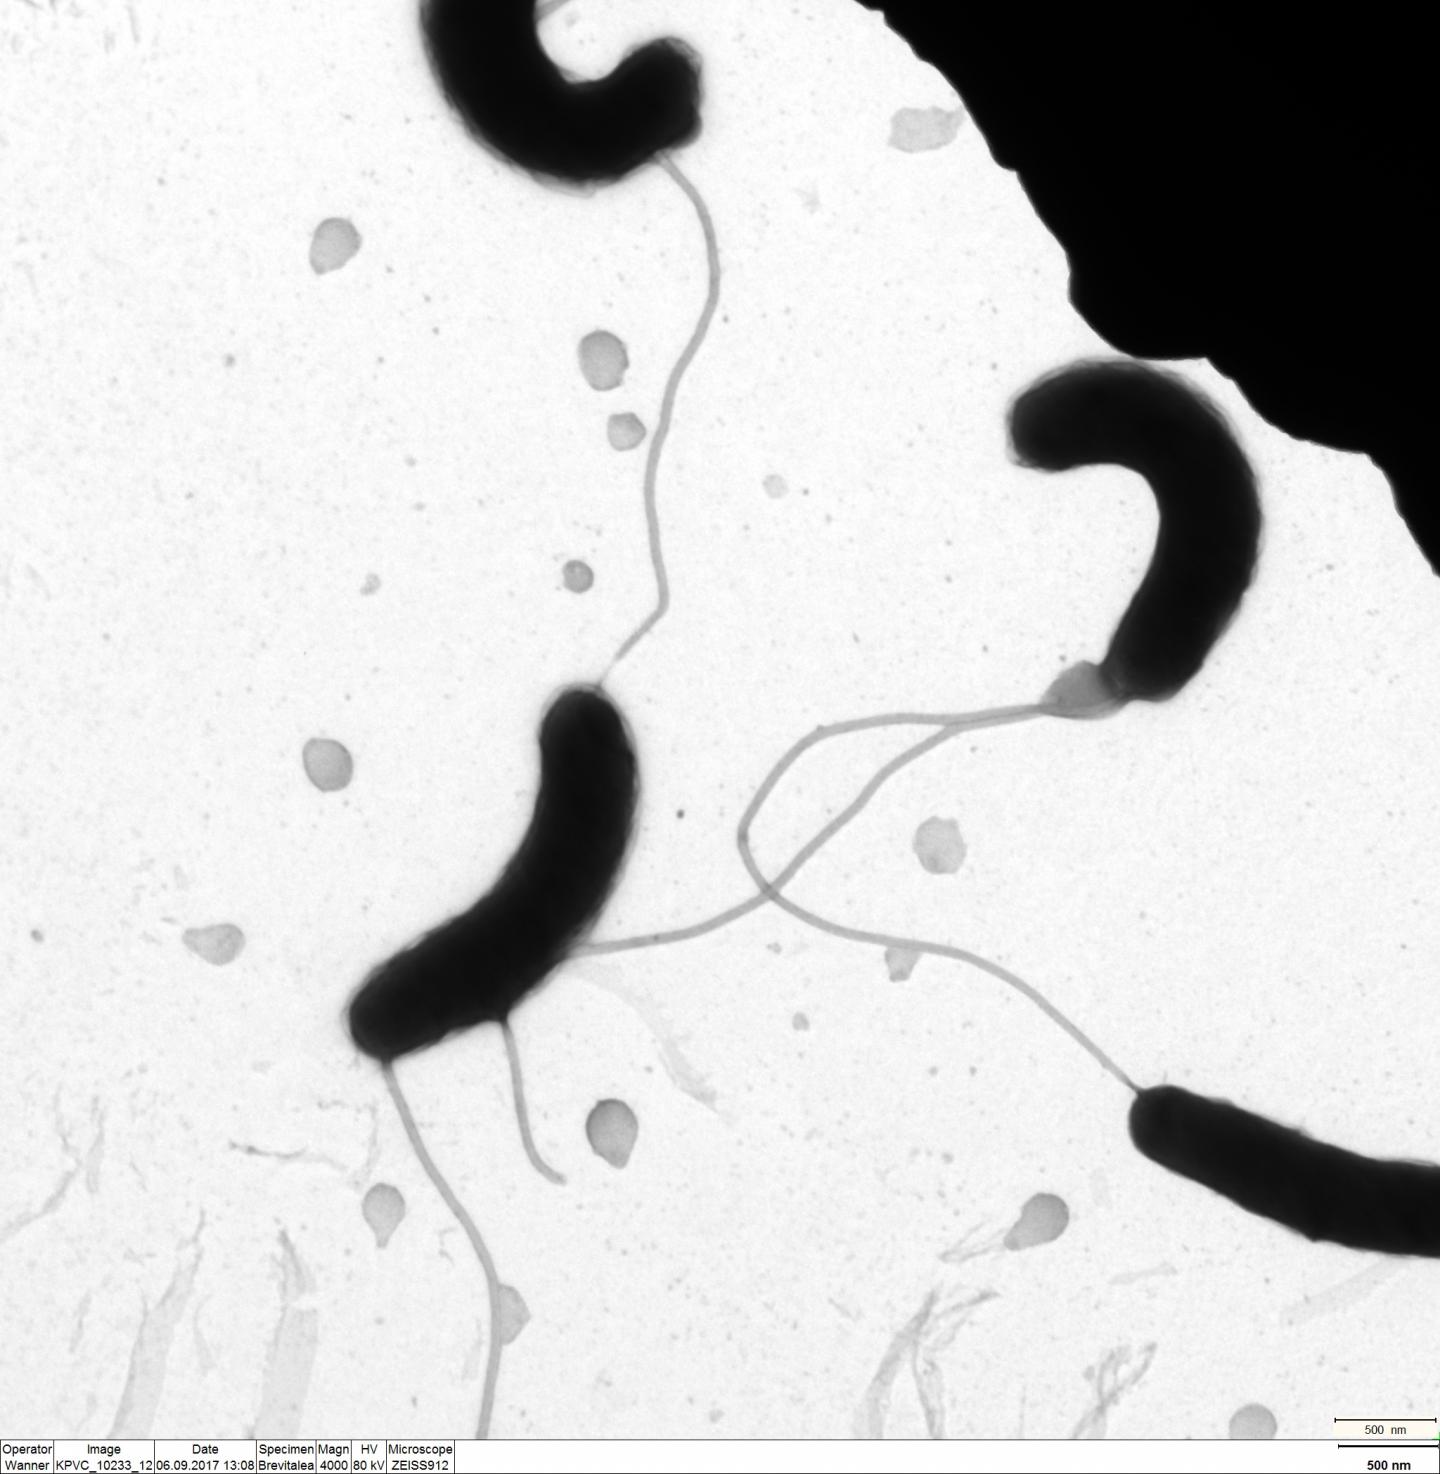

image: Cholera bacteria under the microscope.

The protein CrvA is found in the periplasmic space of the bacterium. This lies between the outer cell wall and the basic substance of the cell, the cytoplasm, which is also surrounded by a membrane. There CrvA determines the curvature of the rod-shaped bacterium V. cholerae. "Until now, however, it was not known what controls the activity of this protein. With the small ribonucleic acid VadR we were able to identify a post-transcriptional inhibitor of the synthesis of this protein," says Prof. Papenfort. In contrast to messenger RNA, small ribonucleic acids do not contain any genetic information, but do influence its expression - usually after the DNA has been transcribed into messenger RNA.